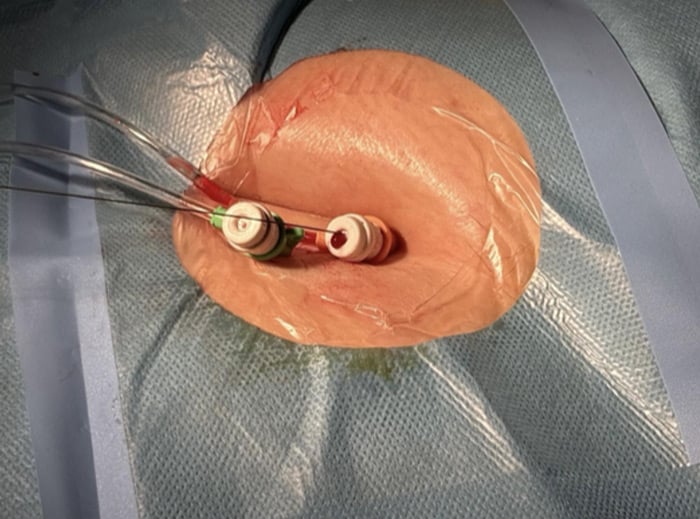

Step 5: deploy the pre-closure suture devices (ProStyle)

- Over the wire, deploy two ProStyle as a pre-closure device and leave the sutures untied (Figure 8).

- Secure suture ends to avoid tangling during exchanges.

- Exchange to the large-bore sheath over a stable wire.

Figure 8: Axillary access with Prostyle positioned and 10Fr in place